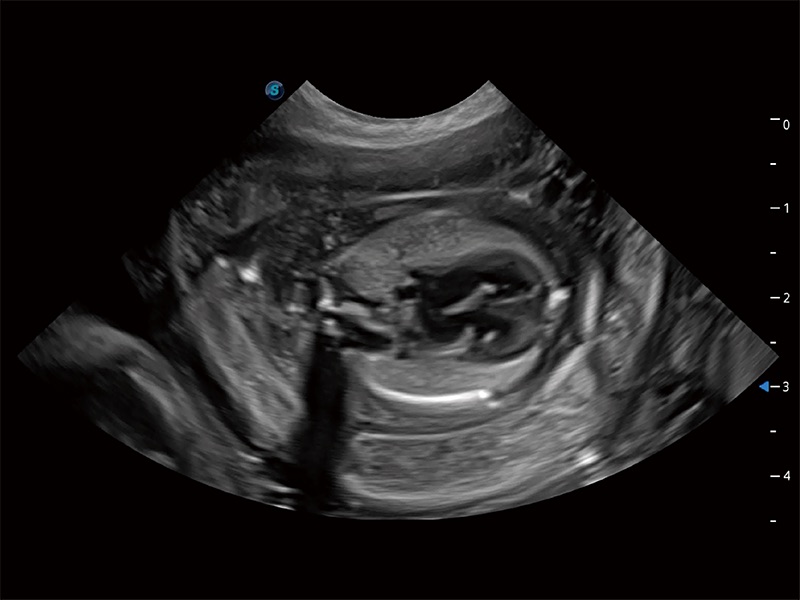

动物是人类最亲密的朋友和最值得信赖的伙伴。美狮贵宾会官网也一直致力于探索动物专用的超声影像解决方案。全新推出的ProPet系列,是美狮贵宾会官网在动物超声影像智能化、专业化、精准化的一次跨越式革新。动物不能用言语来表述自己的不适,通过超声影像,ProPet系列搭建了动物医生与不同物种沟通的“桥梁”,为动物医生注入了“治愈之力”。 ProPet 80 是美狮贵宾会官网匠心打造的一款高端动物专用彩超,采用性能卓越的全新硬件架构,极大提升超声系统的运行效率和数据处理能力,帮助动物医生从容应对日益增多的挑战性病例和日益多样化的临床需求。

高性能和先进的临床应用工具可以为动物医生提供临床信心。ProPet 80 搭载了先进的腹部和浅表应用工具,帮助医生在日常临床实践中发挥前所未有的作用。

ProPet 80 全新的动物超声智能软件和丰富的探头群,为动物医生提供了高清晰度和精细分辨率的图像,无论在宠物、马科、畜牧还是实验室动物等应用中都可以轻松应对,为您的日常工作带来满意的体验。